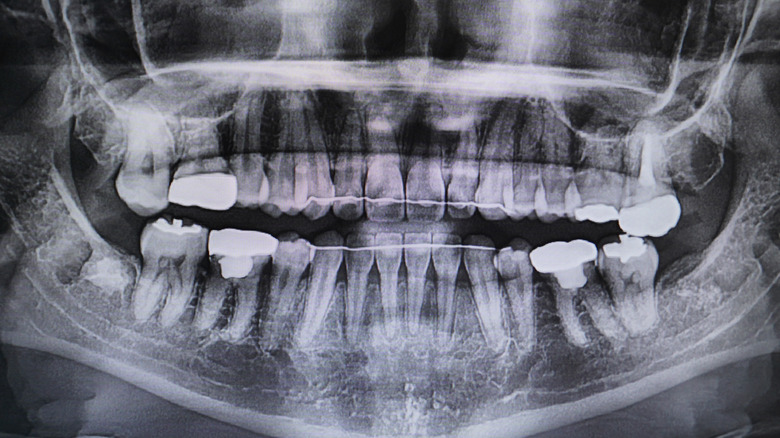

After months or years of having braces, orthodontists give patients 2 options for retainers: permanent or removable. According to Healthline, permanent, or fixed, retainers are made of metal wires and come in different textures, such as smooth or braided. These permanent retainers are then glued onto the teeth with a special bonding agent. While ultimately it's up to the patient, orthodontists recommend permanent retainers to ensure teeth stay aligned. Typically, people who may not be able to keep up with removable retainers may work better with permanent retainers. However, some orthodontists prefer to use a combination of removable or permanent retainers. For example, an orthodontist may recommend permanent retainers for your lower teeth, and a removable retainer for your upper set of teeth.

How long a permanent retainer lasts varies by patient, but according to Stroops Orthodontics Arkansas, permanent retainers can last for up to 2 decades. Despite being "permanent," however, permanent retainers can become damaged and may need to be replaced over time. While this is possible, permanent retainers are still more durable than removable retainers.